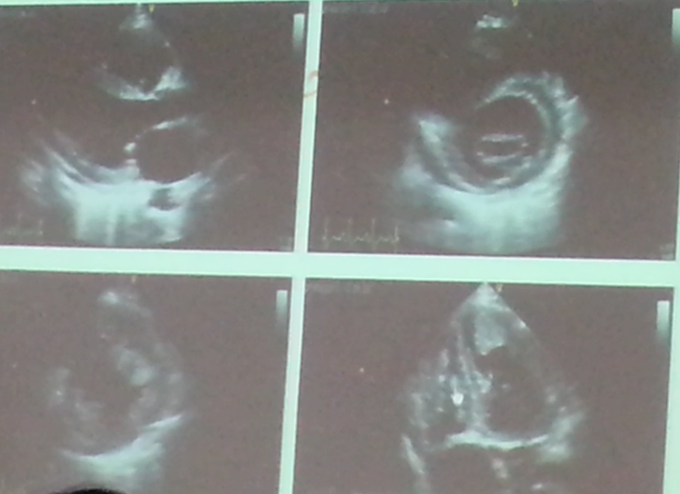

体温36.6,脉搏52次/分,呼吸24次/分,血压140/80mmHg。端坐位,神志清楚,查体合作,唇绀,颈静脉怒张,双肺呼吸音粗,可闻及干鸣音及细湿罗音,心率60次/分,律不齐,第一心音强弱不等,心尖部可闻及2/6级收缩期吹风样杂音。腹平软,无压痛及反跳痛,双下肢重度水肿。 辅助检查:心电图:房颤,完全性左束支传导阻滞,(见下图) 心脏彩超(1年前):左室舒张末期内径80mm,左房内径49mm,EF 36%,全心扩大,以左心扩大为主,心搏减弱,升主动脉增宽,肺动脉压力增高,二尖瓣、三尖瓣轻度关闭不全。 血糖11.93mmol/L,肌酐255umol/L。BNP897.17pg/ml,cTnI 0.06ng/mL。 入院后复查心脏彩超:左房内径34mm,右房四腔径66*54mm,左室舒张末期内径73mm,EF42%。